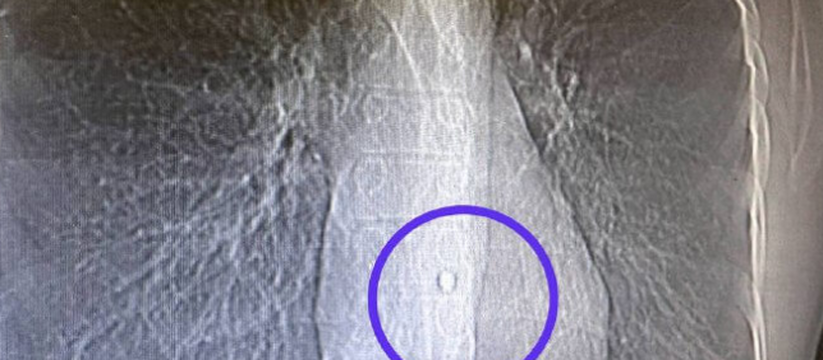

Оказалось, что в марте 38-летний татарстанец получил повреждение легкого от осколочного ранения в грудную клетку. Кроме того, один из осколков залетел в стенку аорты. Бойцу оказывали медицинскую помощь в военных госпиталях Воронежа и Екатеринбурга, однако на операцию направили в Казань.

Операция осложнялась тем, что был риск задеть его сердце.

К счастью, врачи за 2,5 часа извлекли осколок.